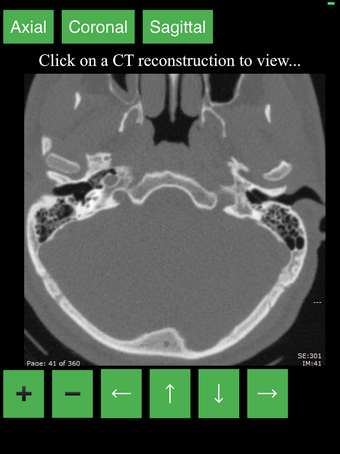

Перекрестные разрезы данных КТ предоставляют динамический и интерактивный метод просмотра поперечной анатомии человека. Вы можете вращать, увеличивать и перемещать изображение, чтобы изучать любую часть тела в деталях.

Перекрестные разрезы создаются с помощью комбинации математических алгоритмов для интерпретации данных из серии сканирований. Результирующие изображения затем преобразуются в серию 2D поперечных срезов и отображаются в специальном приложении для просмотра.